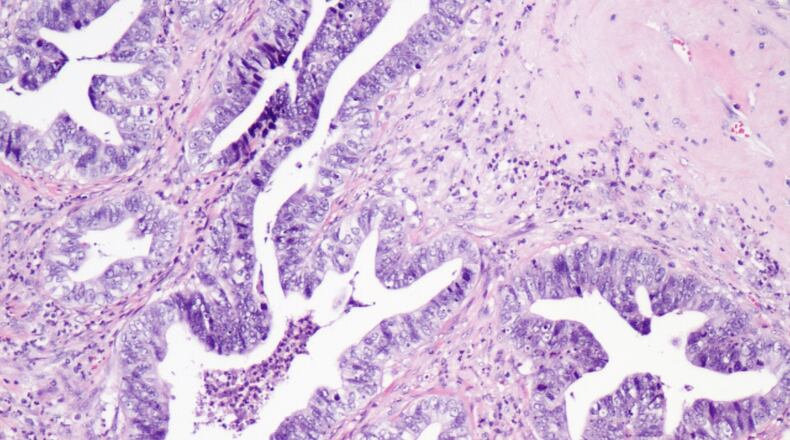

Cervical cancer is caused, in most cases, by the virus called human papillomavirus, or HPV. It can be transmitted through sexual contact. There is a vaccine for women age 26 and younger.